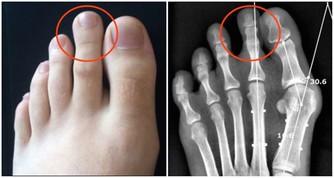

3.商 丘 穴商丘穴屬脾經經穴,正好對應下身淋巴反射區,因此可以治療各種炎症,商丘穴主要消除下身的各種炎症。

因為脾是管運血的,艾灸或者按揉商丘穴,它能把新鮮血液運到病灶上去,髒東西被清走後,炎症自然也就消除了。

主治:腹脹,腸鳴,腹瀉,便秘,消化不良,足踝痛,神經性嘔吐,急慢性胃炎,腸炎,患膀胱炎、尿道炎、盆腔炎等,一定要多揉揉商丘穴,把氣血引下來。

4.丘 墟 穴丘墟穴是膽經的原穴,正好位於足底反射區的上身淋巴反射區,主要消除上身的各種炎症。

丘墟穴專門治療各種上火之症,也就是西醫所說的發炎症狀,比如牙痛發炎、眼睛紅腫發炎、嗓子發炎、咽喉腫痛,頭痛和乳房痛的炎症,跟它就更有關係了。